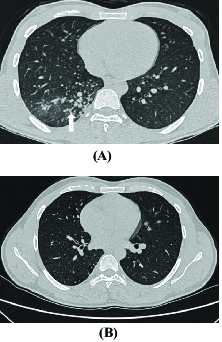

Treatment would include injection laryngoplasty and vocal cord medialisation9 Substantial numbers of patients with vocal cord palsy may develop malignant aetiologies later and. Tree-in-bud opacities appear as tiny centrilobular branching structures on CT most often in the lung periphery which resemble budding trees Figure 18-4. Infiltration by CLL should be added to the.

These are due to filling of the. 1 refers to a pattern seen on thin-section chest CT in which centrilobular bronchial dilatation and filling by mucus pus or fluid. The appearance of a tree in bud is depicted by a pattern of bronchial dilatation and filling on a thin-section chestCT.

Diagnosis of NTM lung infection Underlying conditions Underlying conditions. 1 refers to a pattern seen on thin-section chest CT in which centrilobular bronchial dilatation and filling by mucus pus or fluid resembles a budding tree Fig. Contrast-enhanced CT computed tomography thorax revealed tree-in-bud TIB opacities.